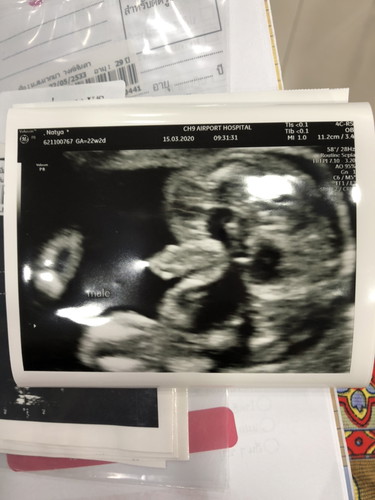

ทีมกรกฎาคมจ้า ชัดเจนมากเลยจ้า..น้องเพศชายค่ะ❤️?

บ้านนี้22กรกฎา63ได้ผู้ชายเหมือนกันค่ะแม่👶🥰

8 ก.ค ชายเหมือนกันเลยจ้า ยินดีด้วยนะคะ

บ้านนี้ 22 กรกฏา ผู้ชายเหมือนกันค่ะ